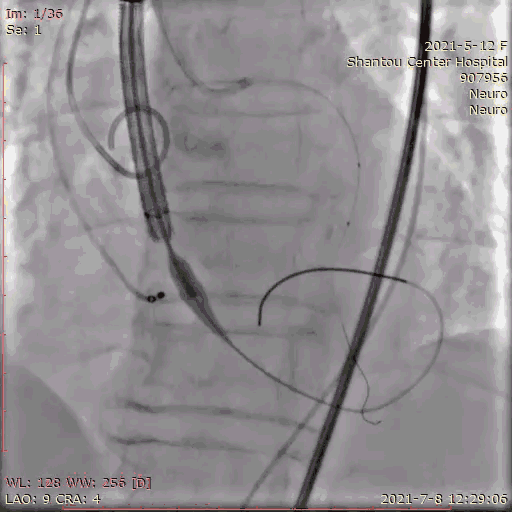

冠脉保护

指引导管将保护球囊送入左冠,防止紧急冠脉堵塞,若瓣膜释放后左冠灌注不良,则行开窗/烟囱植入冠脉支架。

送入输送系统

输送系统定位